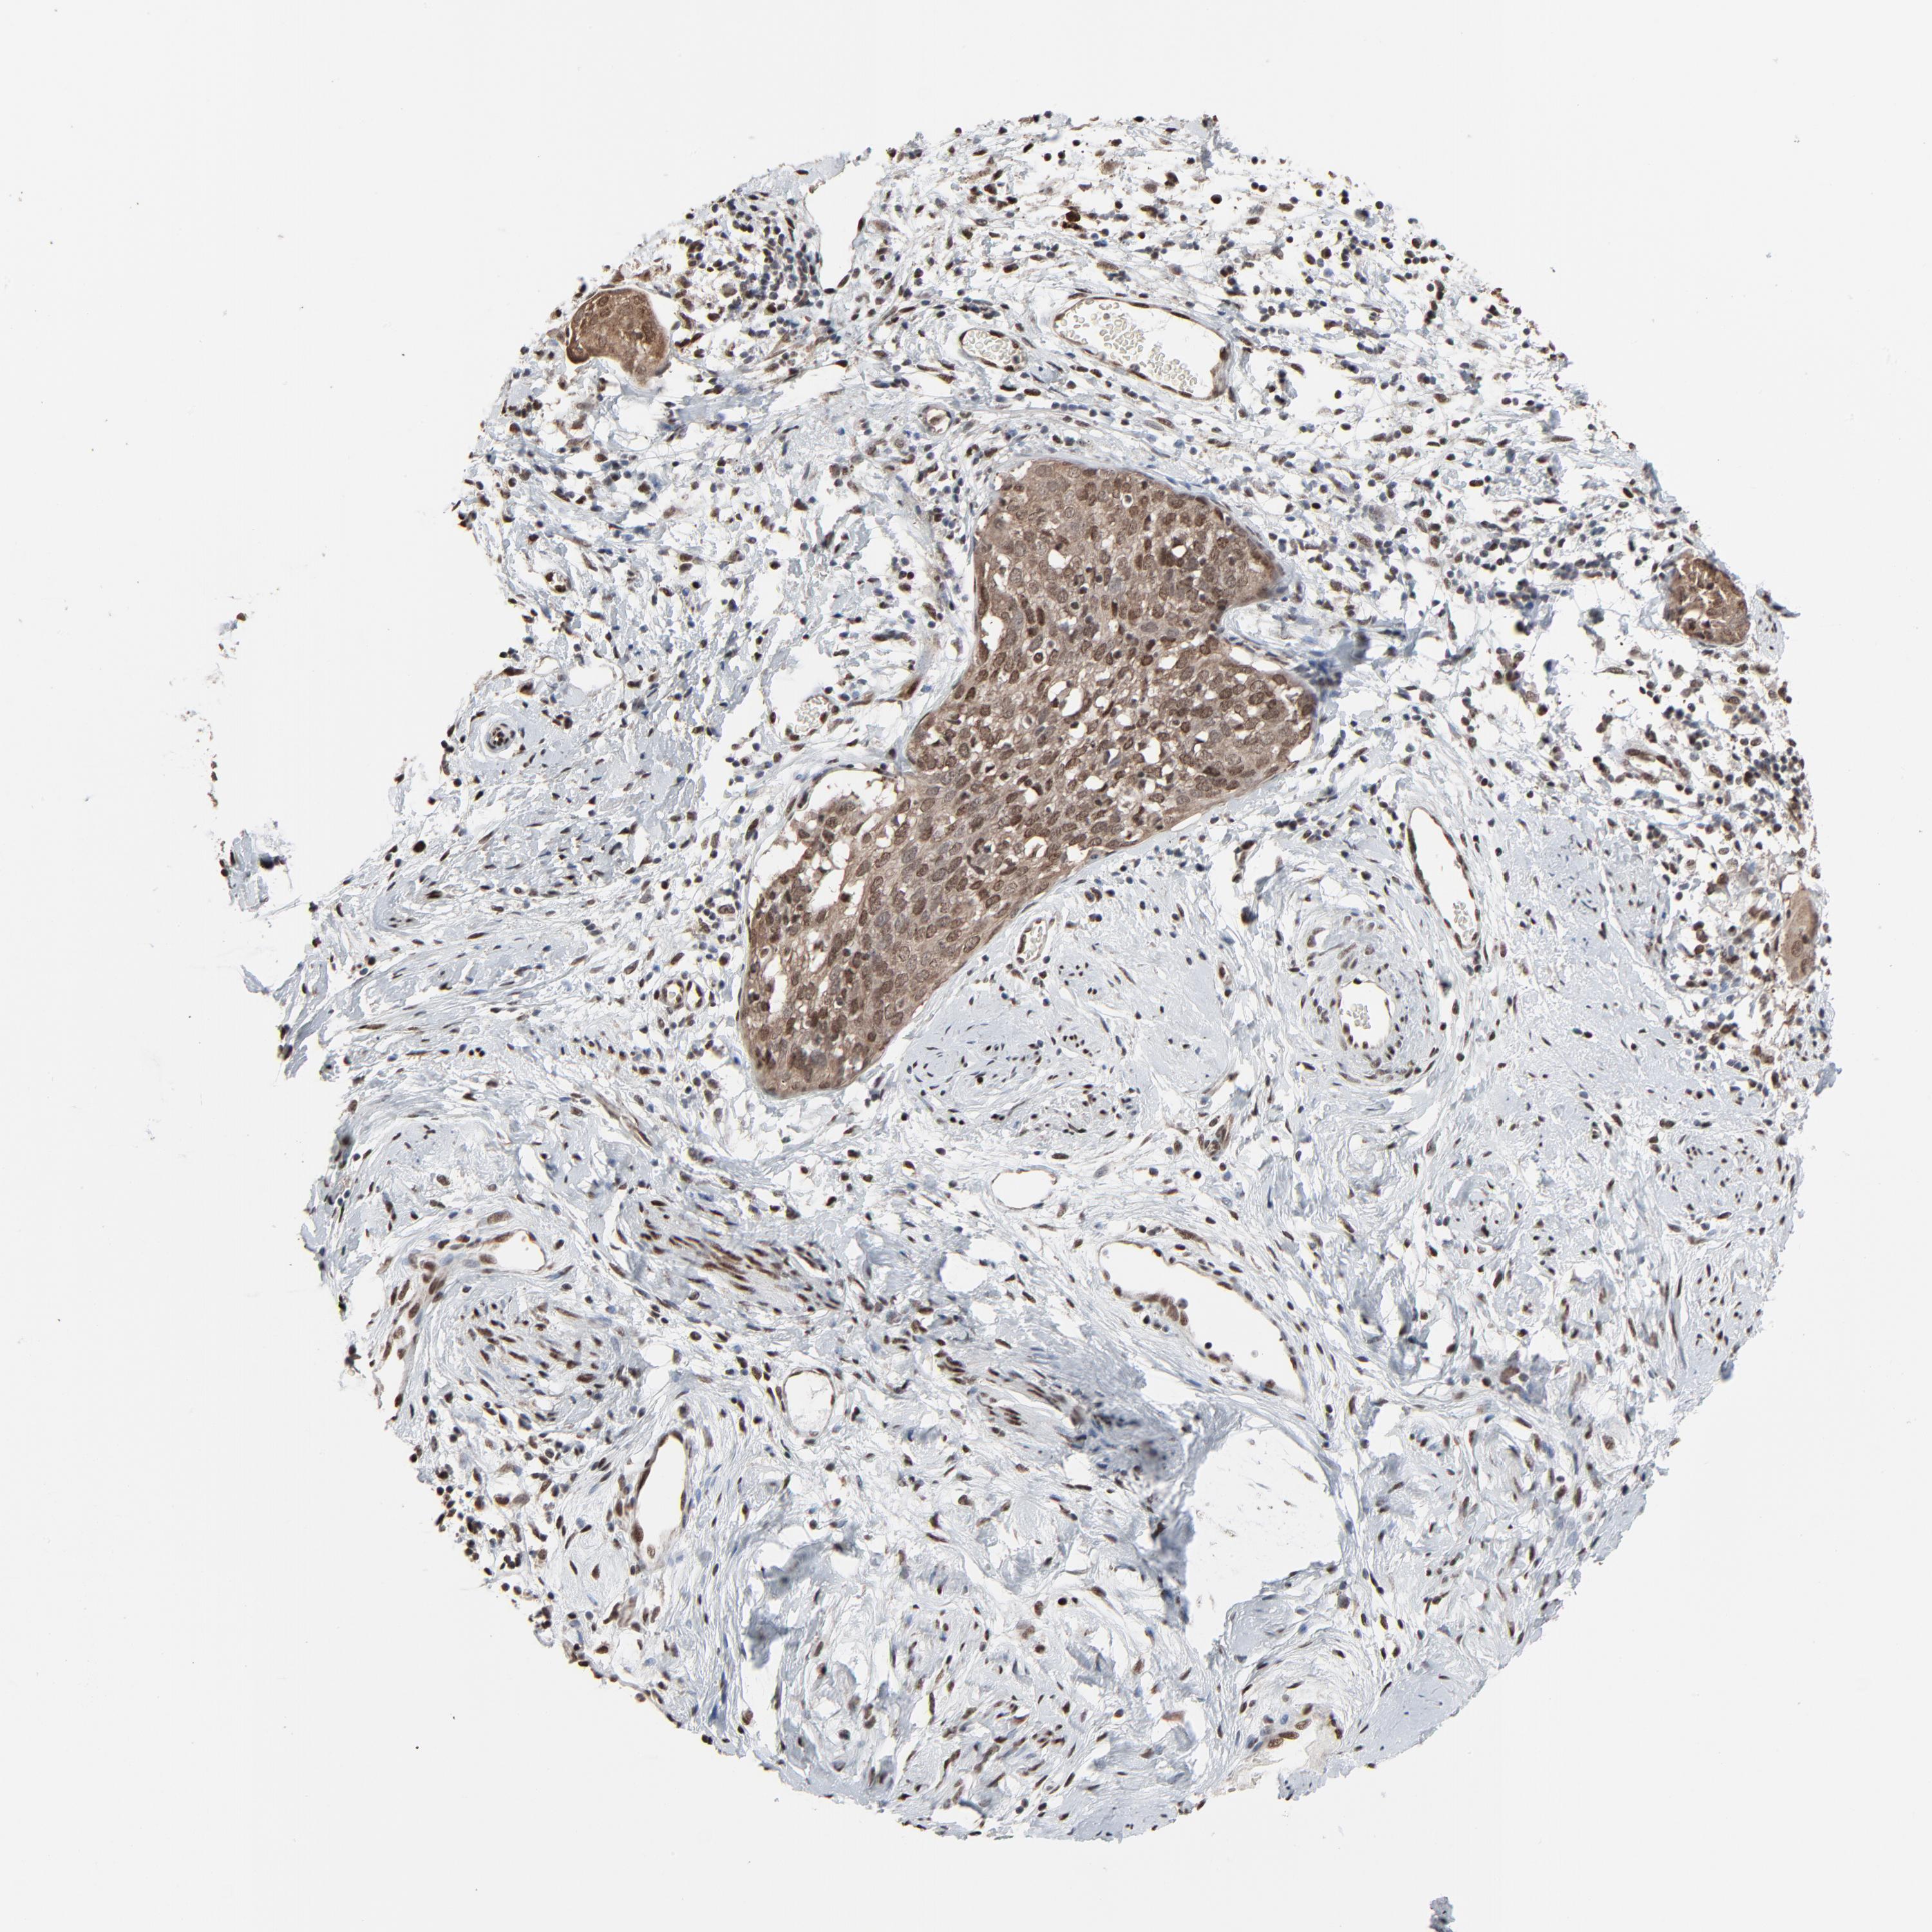

CERVICAL CANCER - Protein expressioni

A mouse-over function shows sample information and annotation data. Click on an image to view it in a full screen mode. Samples can be filtered based on level of antibody staining by selecting one or several of the following categories: high, medium, low and not detected. The assay and annotation is described here.

Antibody stainingi

Antibody staining in the annotated cell types in the current human tissue is reported as not detected, low, medium, or high, based on conventional immunohistochemistry profiling in selected tissues. This score is based on the combination of the staining intensity and fraction of stained cells.

Each image is clickable and will lead to virtual microscopy that enables deeper exploration of all samples and also displays staining intensity scores, fraction scores and subcellular localization as well as patient and tissue information for each sample.

Antibody CAB004999

High

Intensity

Strong

Quantity

>75%

Location

Nuclear

Squamous cell carcinoma, NOS

Adenocarcinoma, NOS